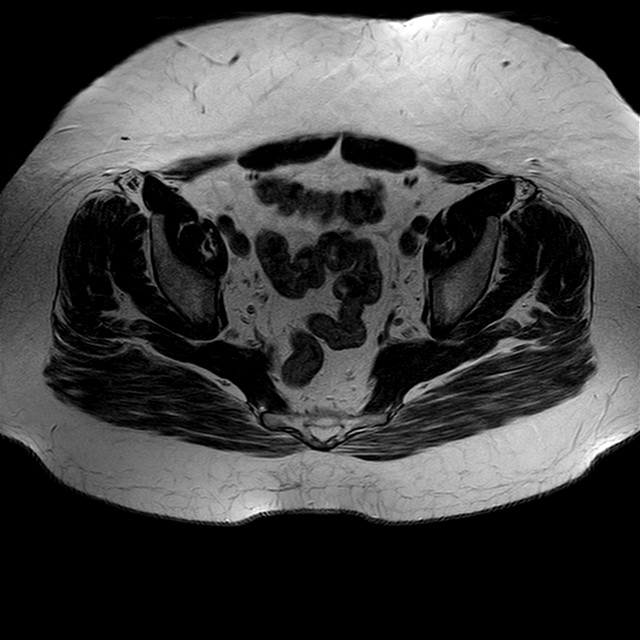

Esami: RMN BACINO

eT2w TSE

Evidenti e simmetriche alterazioni osteofitosiche in regione coxo femorale con riduzione delle rime articolari. Degenerazione completa del cercine glenoideo. Non attuali segni di versamento articolare. Non segni di edema osseo che escludono attuale algodistrofia od osteonecrosi. Lieve e simmetrica riduzione del trofismo della muscolatura glutea.